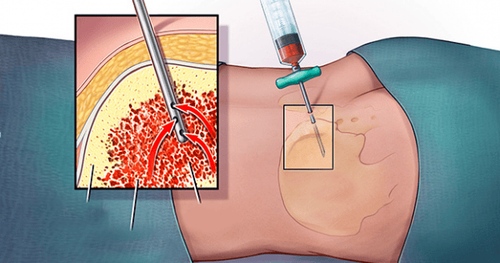

4.1 Hóa trị tân bổ trợ

Nghiên cứu đã chỉ ra rằng khi ung thư vú bộ ba âm tính được điều trị bằng hóa trị trước khi phẫu thuật - gọi là hóa trị tân bổ trợ - thì sẽ có đáp ứng hoàn toàn trên giải phẫu bệnh, sống còn không bệnh và sống còn toàn bộ tốt hơn.

Một cách để đánh giá hiệu quả của điều trị tân bổ trợ là xem các mô bị loại bỏ trong quá trình phẫu thuật có bất kỳ tế bào ung thư hoạt động nào không. Nếu không có tế bào ung thư hoạt động, các bác sĩ gọi đó là đáp ứng bệnh hoàn toàn hay pCR.